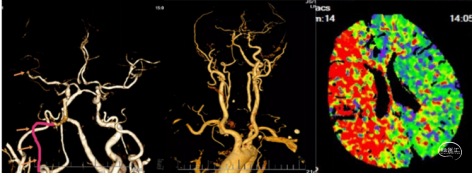

典型病例4 大脑中动脉M3段闭塞抽吸导管血管再通治疗

患者,男,68岁,主诉:突发言语不清伴右侧肢体无力2.5小时。

病史:患者入院2.5小时前休息时突发言语不利,难以与人交流,能理解他人言,右侧肢体无力,口角歪斜,行走、持物不能;双眼向左侧凝视。于11:30至我院急诊就诊,急查头颅CT未见颅内出血;CTA+CTP示左侧大脑中动脉M3闭塞,存在缺血半暗带。

既往史:高血压、房颤病史,未系统服药治疗。

神经系统查体:构音欠清晰。右侧鼻唇沟变浅,示齿、伸舌不合作,咽反射存在,左上肢肌力Ⅴ级,左下肢肌力Ⅴ级,右上肢肌力0级,右下肢肌力0级,肌张力减低,右侧巴彬斯基征阳性,克氏征阴性。NIHSS14评分。

诊断:急性脑梗死(左侧大脑半球);TOAST分型:心源性栓塞。

术前CTA

手术过程

1、行右侧股动脉穿刺并置入8F动脉鞘成功。造影发现左侧大脑中动脉M3段以

远显影欠佳。正位不清晰,斜位清晰可见M3闭塞。

2、5F 125cm 中间导管抽吸:

泥鳅导丝引导8F导引导管至左侧颈内动脉C1远端平直处建立通路,微导丝引导微导管及5F 125cm 中间导管到达左侧大脑中动脉M3闭塞段近端。

近端使用60mL注射器手动抽吸两次,未见血栓取出。可能为导管未能接触血栓。

注意: 6F 125cm 中间导管到达大脑中动脉M1段; 5F 125cm中间导管到达大脑中动脉M2分叉以远。

3、换用3MAX 抽吸导管通路组合:

8F MPA+3MAX抽吸导管+微导丝,抽吸两次后栓子逃逸至远端分叉部。

5、 再次跟进3MAX抽吸一次,完全再通。

术后即刻复查XperCT未见出血。

术后第二天查看患者:神志清楚,应答切题,构音欠清晰。右上肢肌力2级,右下肢肌力3级。NIHSS评分8分。